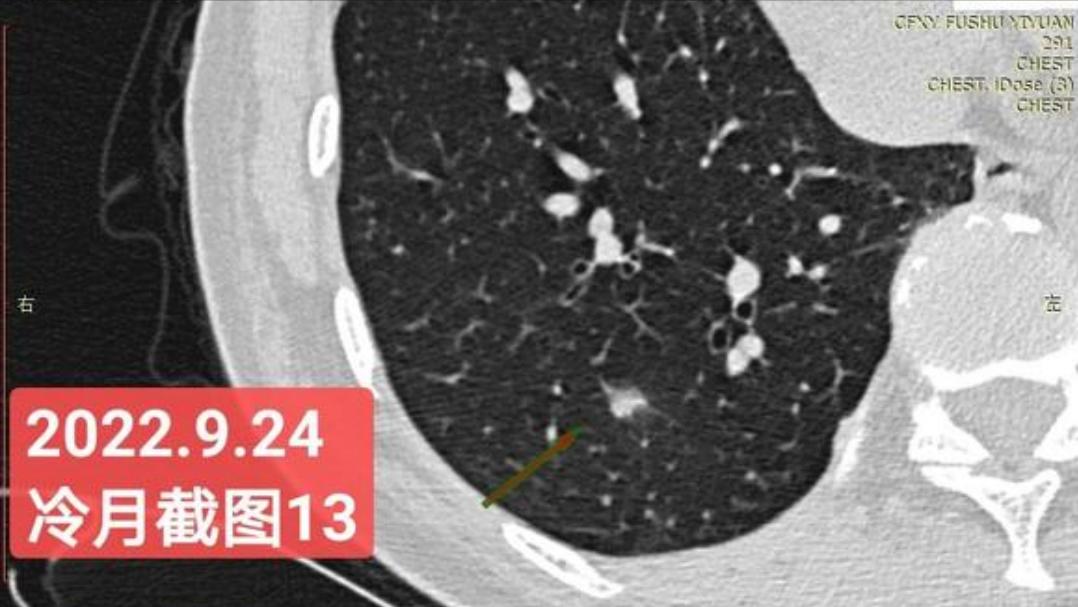

非常感谢戴主任和冷月等几位吧主的无私奉献,你们牺牲自己的休息时间,为广大患者排忧解难,你们对待病人,如同亲人一样,真的好感动!上次,在贴吧里咨询过戴主任关于我的肺结节情况,戴主任说,我右肺下叶那个结节高危。心里好害怕,距离上次CT间隔三个月,我又做了肺部CT,这次还要劳烦戴主任以及吧主们,帮我看看我的肺结节,严重吗?需要马上手术吗?

我昨天把我五次肺部CT电子版以及报告,发给了冷月吧主,昨天晚上,冷月吧主就为我截好图,发给我,非常令我感动,谢谢您冷月吧主,您辛苦了,您要多休息,不要太辛苦了。

我是21年7月做肺部CT,报告给报出0.5厘米肺结节。(但大夫说,20年就已经有那个肺结节了,因为小,报告没给报)。自发现肺结节后,吃了四个月中药,结节没有缩小,反而增大了。今年8月1日开始到现在,又吃了近两个月的蒙药了。 结节还是没有缩小,反而在增大。21年7月到现在,复查过3次肺部CT了。结节一直在增大。最近一次复查时间是2022年9月24日。

上次找戴主任贴吧咨询过,主任说我右肺下叶那个结节高危,距离上次CT,到现在三个月复查肺部CT。所以9月24日又复查做了肺部CT。

右下肺结节高危,肺窗已经到亚实性阶段CTR>0.5,纵膈窗可见实性,目前已经不属于异质混磨,而且PSN亚实性结节。